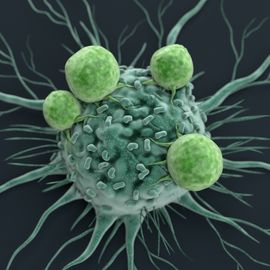

Cancer Immunology

This page provides educational resources, events, news and products related to cancer immunology. Content will cover aspects from the tumor immune environment and immunosurveillance, to cancer immunotherapies and vaccines.